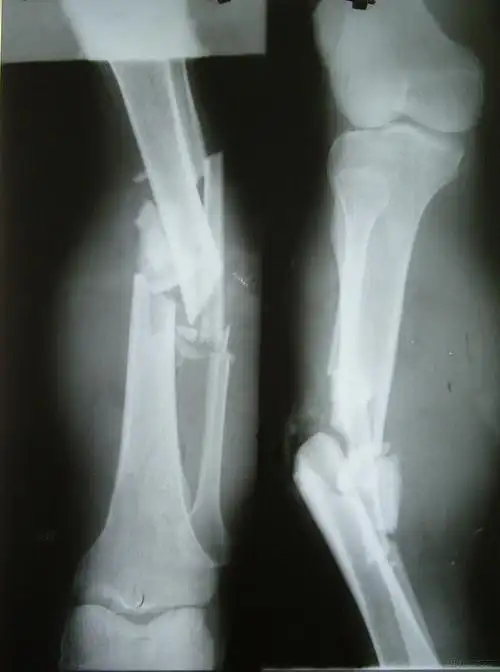

左股骨粗隆下骨折

左胫腓骨开放性骨折

左胫腓骨开放性多段骨折

创伤左小腿开放性骨折